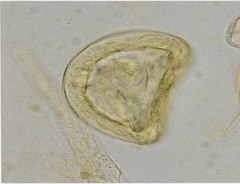

Describe the morphology of A. perfoliata eggs.

D-dhaped

~50-80 um

Onchosphere is supported by pyriform apparatus